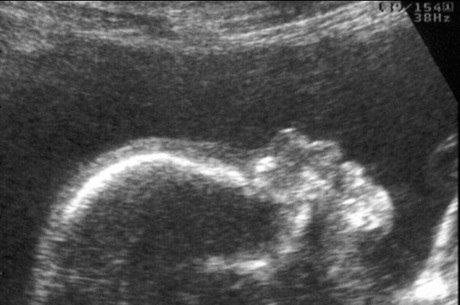

Um bebê húngaro sobreviveu três meses no útero de sua mãe que foi declarada em estado de morte cerebral e que os médicos mantiveram viva com ajuda de aparelhos o tempo suficiente para que o feto terminasse de crescer, informa nesta quinta-feira o jornal Népszabadság.

A mãe sofreu um derrame no cérebro na 15ª semana de gravidez e teve morte cerebral, mas os médicos mantiveram suas funções vitais ativas até que em julho o bebê nasceu por cesariana, após sete meses de gravidez.

Durante três meses, a gestação continuou com o organismo da mãe sob rigoroso controle, em temperatura controlada e a irrigação sanguínea ativa.